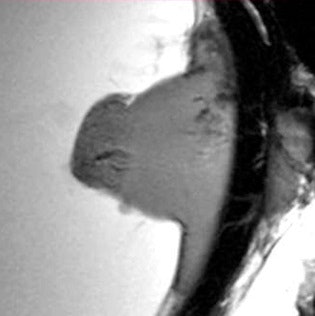

MRI units of 7.1-tesla and more, used for research purposes and termed ultrahigh-field MRIs, can achieve resolutions of 40 micrometers and less. Using thin slice settings, radiologists can see images that used to be available only for tissue placed under the microscope. Cells and tiny blood vessels are visualized based on MR microscopy, with no biopsy required.

Dr. Paul-Christian Krüger and his team at the Institute for Diagnostic Radiology and Neuroradiology of the University Hospital in Greifswald have demonstrated the potential of the method. In a study conducted in collaboration with the ophthalmology clinic of the University Hospital of Rostock, they examined ten eyes resected because of malignant tumors of various types. They then compared results to those from histological analysis carried out at Rostock's pathology department.

"MR microscopy visualizes the eye and its surrounding lipid tissue. This permits us to ascertain whether a tumor is growing into the surrounding tissue or not, which can play a decisive role in designing a therapy," he noted at the meeting. "Histological interpretation of the tumors produced, for all cases, identical results as in MR microscopy. For example, pathologists established that two tumors had grown into the surrounding tissue, congruent with our previous diagnosis based on MR microscopy."